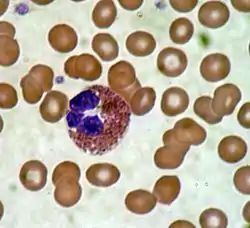

Eosinophil under the microscope (400×) from a peripheral blood smear. Red blood cells surround the eosinophil, two platelets at the top left corner. | |

These cells are eosinophilic or "acid-loving" due to their large acidophilic cytoplasmic granules, which show their affinity for acids by their affinity to coal tar dyes: Normally transparent, it is this affinity that causes them to appear brick-red after staining with eosin, a red dye, using the Romanowsky method.[4] The staining is concentrated in small granules within the cellular cytoplasm, which contain many chemical mediators, such as eosinophil peroxidase, ribonuclease (RNase), deoxyribonucleases (DNase), lipase, plasminogen, and major basic protein. These mediators are released by a process called degranulation following activation of the eosinophil, and are toxic to both parasite and host tissues.

In normal individuals, eosinophils make up about 1–3% of white blood cells, and are about 12–17 micrometres in size with bilobed nuclei.[3][5] While they are released into the bloodstream as neutrophils, eosinophils reside in tissue.[4] They are found in the medulla and the junction between the cortex and medulla of the thymus, and, in the lower gastrointestinal tract, ovaries, uterus, spleen, and lymph nodes, but not in the lungs, skin, esophagus, or some other internal organs under normal conditions. The presence of eosinophils in these latter organs is associated with disease. For instance, patients with eosinophilic asthma have high levels of eosinophils that lead to inflammation and tissue damage, making it more difficult for patients to breathe.[6][7] Eosinophils persist in the circulation for 8–12 hours, and can survive in tissue for an additional 8–12 days in the absence of stimulation.[8] Pioneering work in the 1980s elucidated that eosinophils were unique granulocytes, having the capacity to survive for extended periods of time after their maturation as demonstrated by ex-vivo culture experiments.[9]